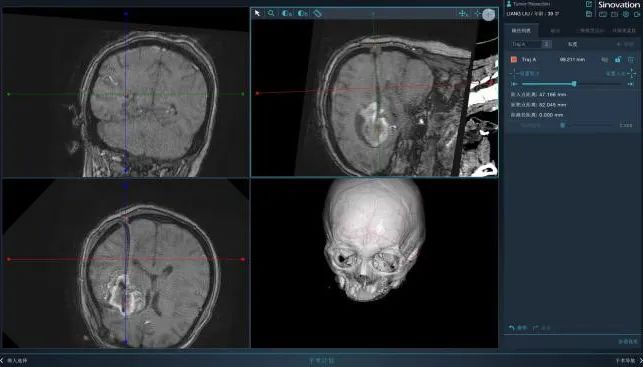

团队在上海长征医院侯立军教授的5G远程指导和徐涛副主任医师现场支持下,通过北京医疗设备华科精准Q300手术机器人辅助开展了精准的颅内血肿微创引流术,成功救治了患者。